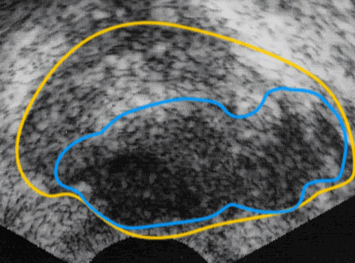

経直腸的超音波(エコー)検査

超音波検査では、肛門から棒状の超音波探子(プローブ)を直腸に挿入し、前立腺の内部を画像で観察します。がんがある場合、黒い影として映し出されます。また、前立腺の被膜が鮮明でない場合や形が左右対称でない場合などにがんが疑われます。

経直腸的超音波検査画像

• 前立腺

• 前立腺がんの被膜外浸潤部分